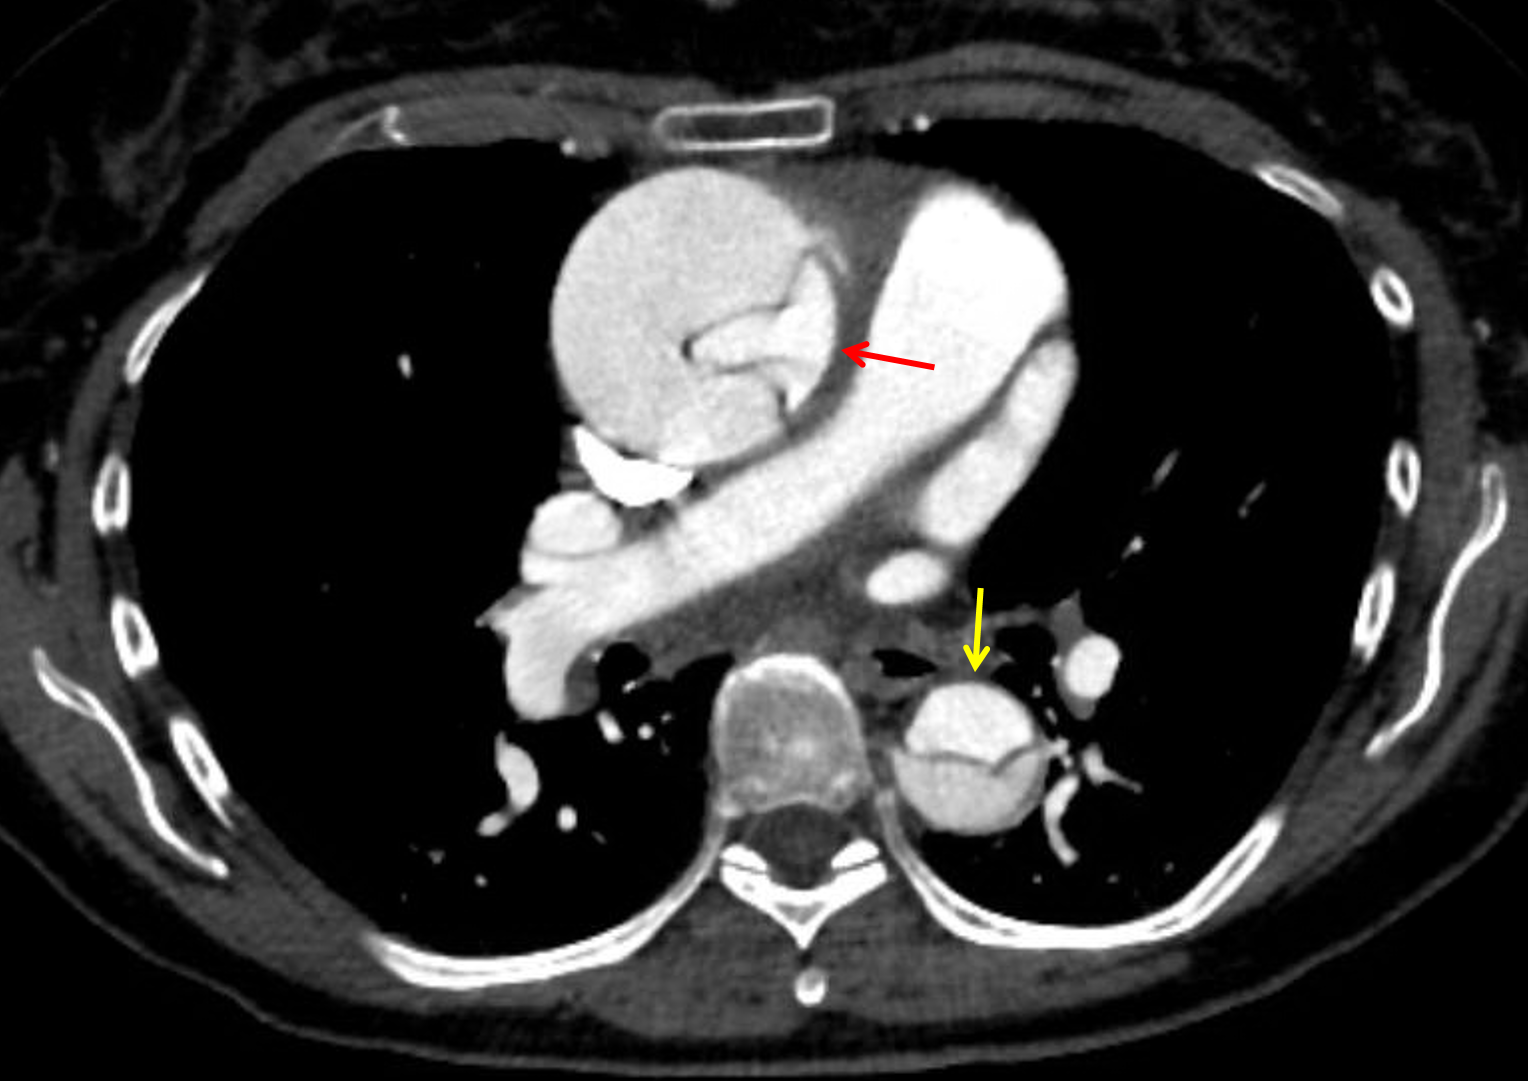

Age: 67

Sex: Female

Indication: Chest pain, stroke-like symptoms

Sample ReportStanford type A aortic dissection originating at the noncoronary cusp of the aortic annulus, which extends through the thoracic and abdominal aorta and terminates in the left common iliac artery. Resultant aneurysmal dilation of the ascending aorta measuring up to 5.9 cm. The coronary arteries arise from the true lumen and are patent. No hemopericardium or hemothorax.

Dissection extends into the arch vessels with notable occlusion of the proximal right common carotid artery and severe narrowing of the brachiocephalic artery and right subclavian artery.

A linear intraluminal hypodensity in the proximal left common carotid artery may be artifactual, though a focal dissection at this location is not excluded. Recommend attention on followup imaging.

Mesenteric vessels arise from the true lumen and are patent, though there is a contribution to the celiac artery from the false lumen. Focal high grade narrowing of the proximal celiac artery due to median arcuate ligament compression and of the proximal SMA due to atherosclerotic plaque.